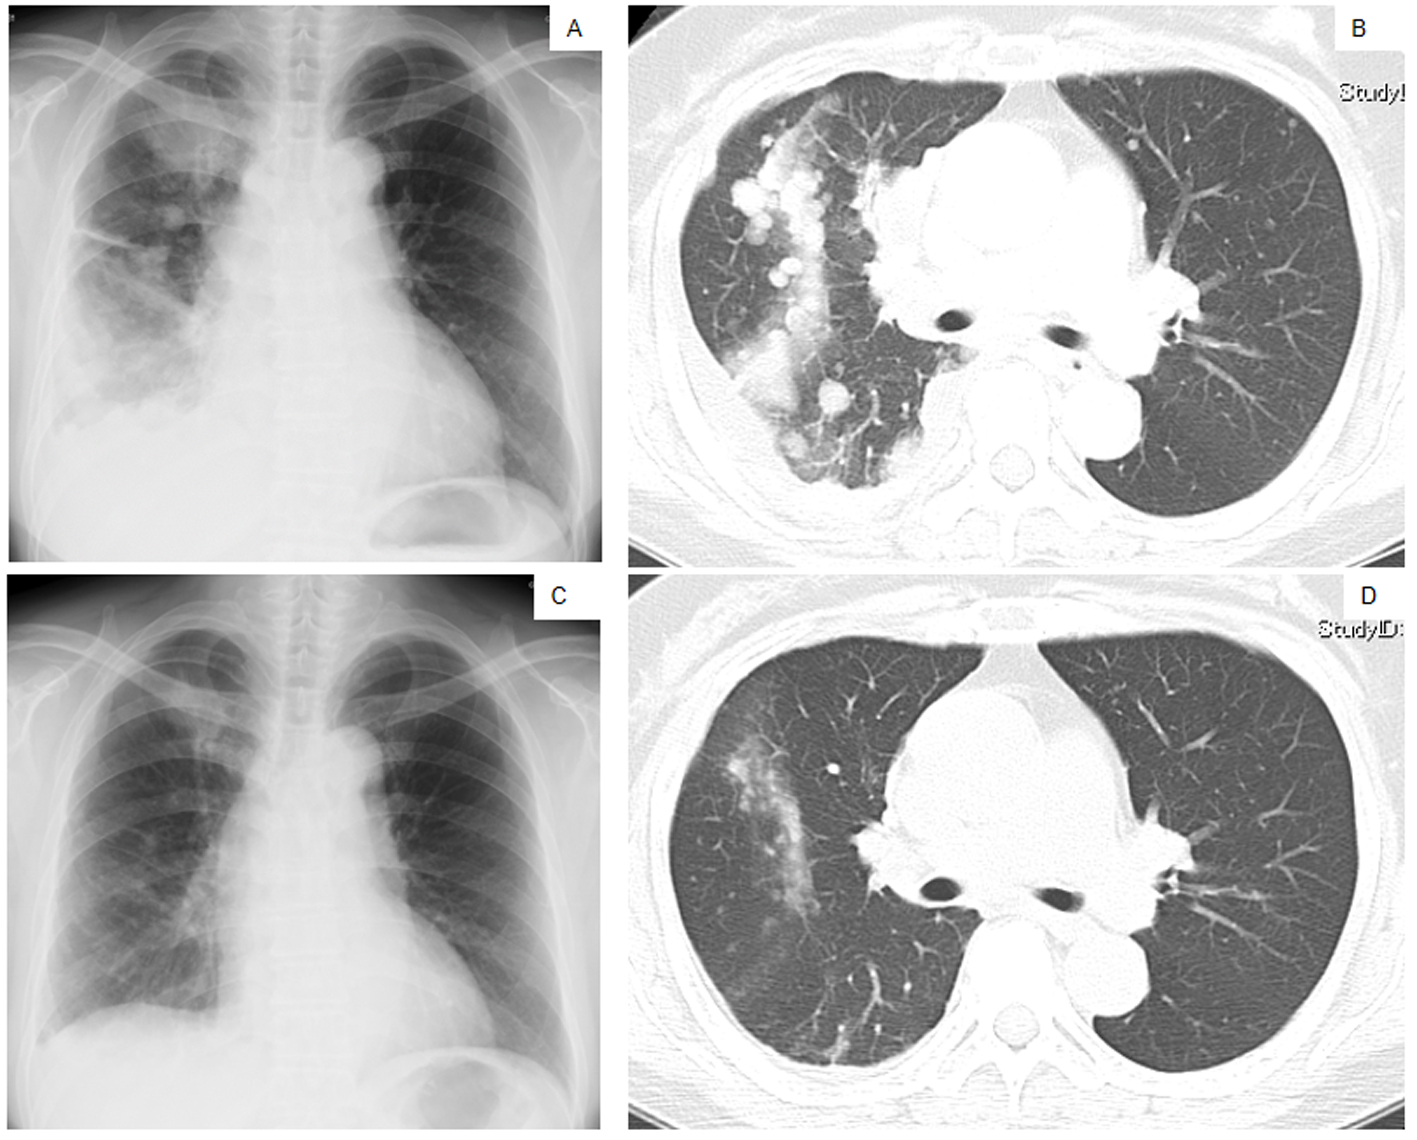

A 60-year-old Japanese woman who had never smoked was referred to our hospital in March 2010 because of a persistent cough and left subclavicular lymphadenopathy. A chest X-ray (Fig. 1A) and a computed tomography (CT) scan (Fig. 1B) showed multiple nodules in both lungs. The patient did not present with any neurological symptoms, although an enhanced brain CT scan revealed multiple metastatic nodules in the brain. According to the results of a cytological examination of a bronchial lavage and radiographic investigations, she was diagnosed with pulmonary adenocarcinoma (cT4N3M1, stage IV). The serum amylase level was elevated (1,531 IU/L; normal level ≤ 106 IU/L), and amylase isozyme patterns identified the salivary type as the most abundant (94%). The pancreas and salivary glands were unlikely to have had any clinical involvement in the development of hyperamylasemia. At that time, we failed to immunohistochemically demonstrate amylase production in cancer tissue because of small number of cancer cells in the bronchoscopical sample. The level of carcinogenic embryonic antigen (CEA) was within the normal range. An EGFR L858R point mutation was detected in exon 21 from the bronchial lavage specimen using the peptide nucleic acid-locked nucleic acid polymerase chain reaction (PNA-LNA PCR) clamp method.

![]() Click for large image | Figure 1. Chest X-ray films (A, C) and a CT scan of the middle lung fields (B, D) taken in April 2010 before first-line chemotherapy using carboplatin plus weekly paclitaxel (A, B), and taken in May 2010 after the second course of the first-line chemotherapy (C, D). |

The patient was treated with a combination of carboplatin (area under the blood concentration time curve, 6 mg/min/mL) plus weekly paclitaxel (70 mg/m2) as the first-line regimen. Her amylase levels rapidly decreased after the introduction of chemotherapy and eventually reached the normal range (Fig. 2). Chest X-ray (Fig. 1C) and CT scan (Fig. 1D) results showed a good partial response to chemotherapy. In March 2011, at 6 months after the last administration of the first-line regimen, multiple metastatic lesions in the lung and brain had increased in size and progression was documented; however, the serum amylase level remained slightly elevated (247 IU/L) (Fig. 2). At the same time, we performed a biopsy of a newly enlarged cervical lymph node metastasis. Immunohistochemical analysis detected anti-salivary type amylase using an antibody against amylase (sheep polyclonal antibody, #BGS0480-0404; Biogenesis, Poole, UK) (Fig. 3B), and the L858R mutant of EGFR was detected using a specific cognate antibody (clone 43B2 rabbit monoclonal antibody; Cell Signaling Technology, Massachusetts, USA) [11] (Fig. 3C).